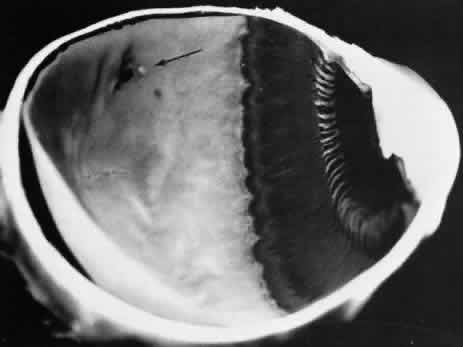

Retinoschisis associated with a bullous architecture and prominent reticular cystoid degeneration has been termed reticular degenerative retinoschisis. Reticular degenerative retinoschisis can be distinguished from typical degenerative retinoschisis by the large extent of retinal involvement, a round or ovoid configuration with bullous elevation of the extremely thin inner layer, and an irregular, pitted outer layer (Figs. 20 and 21). Typical cystoid degeneration is always present anterior to the schisis; reticular cystoid degeneration is usually prominent at some site in the involved eye. Blood vessels coursing through the inner layer give it an arborizing reticular pattern on contact lens biomicroscopy. The intraretinal cavity is optically empty; the outer wall is irregularly excavated to produce a pocked or honeycomb appearance. Round or ovoid holes are often present in the outer retinal layer; they are single or multiple, frequently large, and usually associated with a rolled posterior edge.13

Fig. 20. Reticular degenerative retinoschisis. Note reticulated, highly elevated, inner wall with a conspicuous delicate vascular pattern. Radial columns of the retina are completely disrupted within the region of bullous elevation, and the retinoschisis extends posterior to the equator. (× 18.)

Microscopic sections demonstrate the extremely attenuated, blood vessel-containing inner layer composed of the internal limiting membrane and remnants of the nerve fiber layer (Fig. 22). The honeycomb appearance of the outer layer corresponds to irregular excavations. In some areas, the outer layer is made up of outer plexiform, outer nuclear, external limiting, and rod and cone layers; in other areas it is reduced to only the external limiting and the rod and cone layers; round or ovoid holes may be present (Fig. 23).

Fig. 22. Reticular degenerative retinoschisis. Note complete loss of radial supporting columns of retina and marked elevation of delicate inner wall, which contains fine blood vessels. Outer wall shows periodic exaggerated thinning. (Hematoxylin-eosin; × 60.)

Fig. 23. Reticular degenerative retinoschisis with hole in outer wall and localized retinal detachment. Margins of hole are rolled and covered by a garland of degenerating photoreceptor outer segments. (Hematoxylin-eosin; × 250.)

Reticular degenerative retinoschisis is evident in 1.6% of adult patients, is bilateral in only 16% of these, and thus is noted in 0.95% of adult eyes (see Table 3). The lesion is found most commonly in the inferior temporal quadrant. A band of typical cystoid degeneration always separates the schisis from the ora serrata; the schists usually reaches the equator and often extends appreciably into the posterior retina.